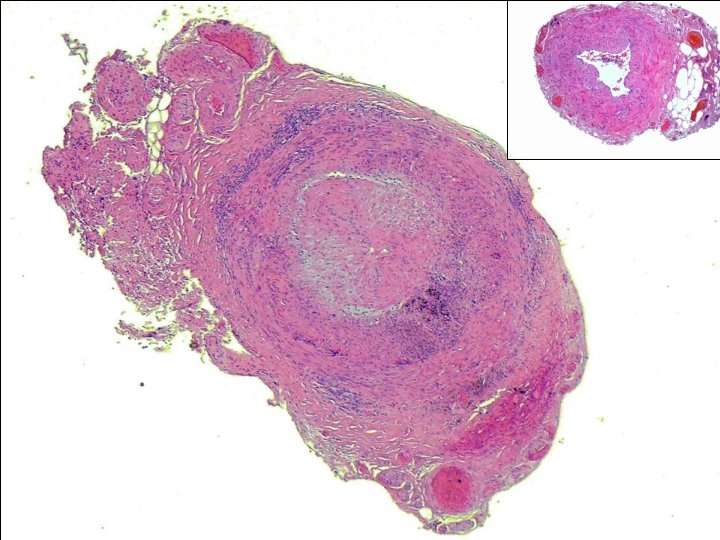

Normal TA intima media adventitia Bluish curly line

Normal TA

intima media adventitia

Bluish curly line is internal elastic lamina

intima media Elastin Von Gieson (EVG) stained internal elastic lamina-normal.

adventitia media

INTIMA MEDIA

EVG STAIN